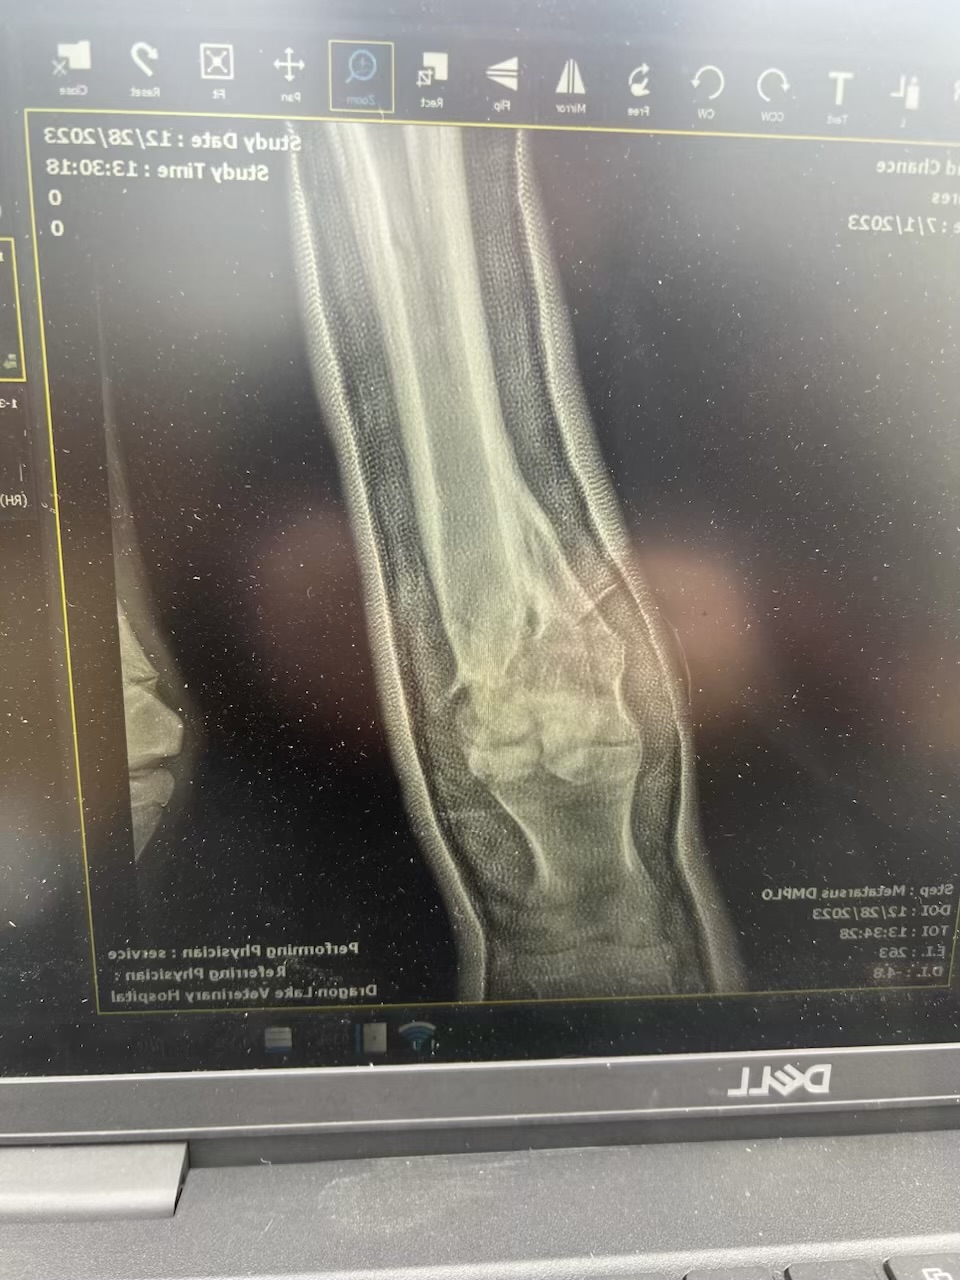

However, Second Chance’s leg was still in a cast that needed to be changed regularly. Three hours from the nearest vet, this wasn’t an easy feat to tackle. Trailering her to the nearest vet would have to be a bi-weekly task, and that wasn’t feasible. With winter setting in, the best move to make was to wean her off her Dam Juno and bring her to a trusted friend and capable veterinarian. Dr. Ginger Langin with Dragon Lake Veterinary Hospital, six hours north of the ranch was the call.

While at Dragon Lake Vet, Second Chance has made fantastic progress. She gets stellar around the clock care including supplements, training and cast changes. When she exhibits healing to a point where she can full weight bear on her hoof and leg without a hard cast, she’ll be able to come home and reunite with her dam, Juno. We think we are close. But we still have to be set up at the ranch to X-ray, change casts and dressings to be able to properly care and support her

You and your family willingness to fight as long as Second Chance will to continued fighting. The xrays tell the store, the truth. Most would have ended it all. To spend the time making phone calls, asking questions, then traveling for days to safely transport her and her mom to Wyoming. Vet’s that were also willing to take on the challenge. Above and beyond, I am not sure you know any other way, to be honest. Second Chance looks unbelievable beautiful, strong and even after all that she has been through you can still see the fight in her sweet soft eyes. When you are around her…. she know you are her Hero and she shows you her love in her behavior around you.